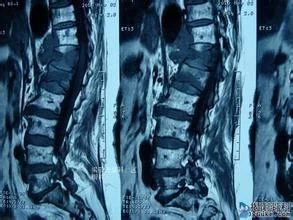

多有明确的外伤史;胸腰局部肿痛 ,外观可有后突畸形 ,局部有压痛及叩击痛 ,腰部活动不利;伴有骨髓损伤者可有不同程度的功能障碍;X 线摄片可明确骨折的类型式容和程度;CT 和 MRI 检查可明确脊髓受压的程度。